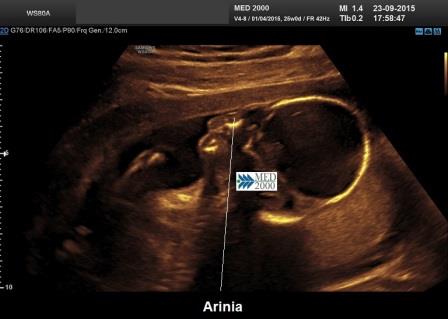

L'Arinia isolata viene spesso diagnosticata solo dopo la nascita (Zemtsov.GE et al., 2023) L’immaging ecografico può rivelare un profilo fetale piatto al secondo trimestre avanzato (Cusick W et al., 2000; Cesaretti C et al., 2011) tuttavia la diagnosi prenatale è possibile solo a partire dalla 23a settimana di gestazione mediante la risonanza magnetica fetale (Li X et al., 2015).

La diagnosi ecografica si basa sulla mancata visualizzazione del naso in scansione sagittale con labbro superiore prominente, mentre in sezione trasversa si osserva una depressione tra le due orbite. Spesso il mascellare è iposviluppato e coesiste palato ogivale (anomalie queste non diagnosticabili in ecografia prenatale).